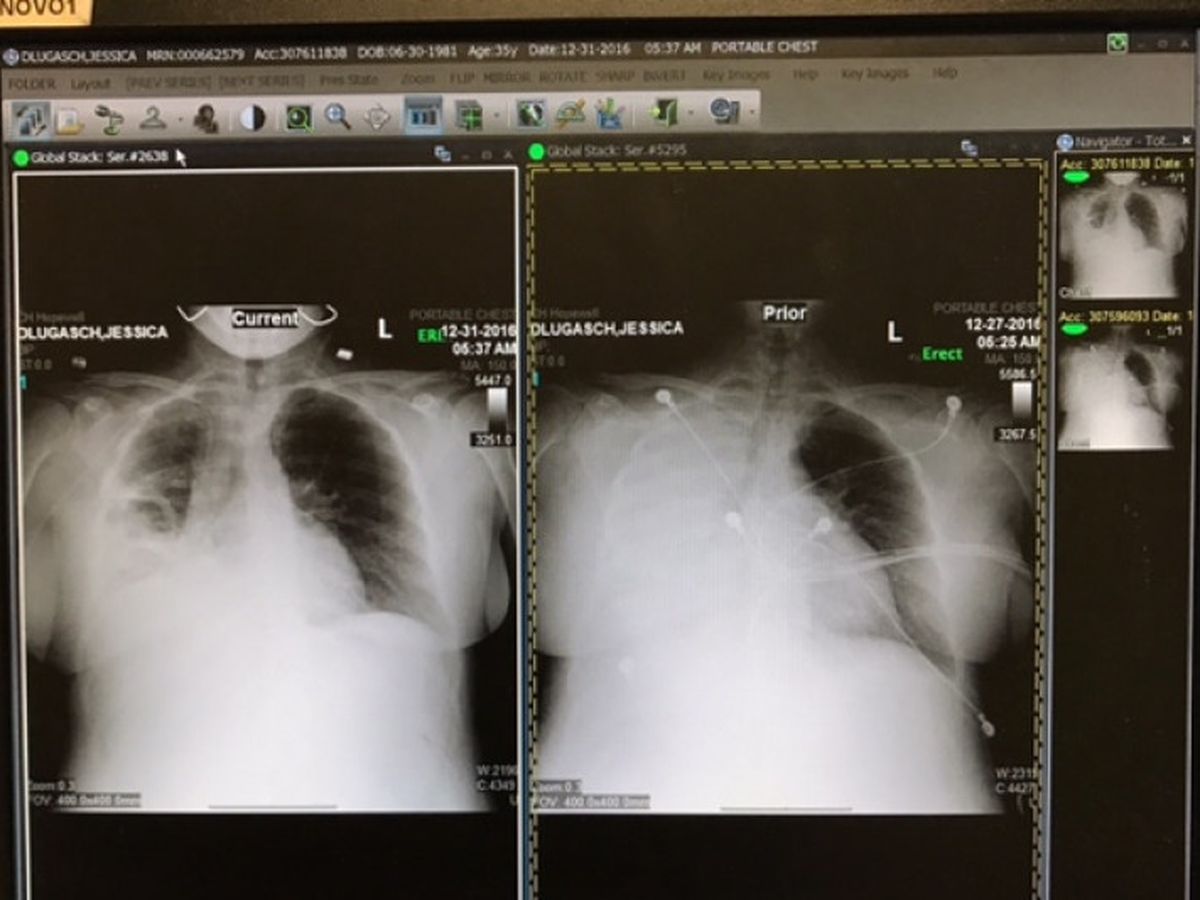

On Christmas day 2016 I almost died of sepsis. Writing down these details is probably one of the hardest things I have ever done. And my husband and I deliberated for quite a while about doing it. But I have children who I need to put first, so I am humbly asking for help. I feel if anyone is going to help me, they deserve the right to know why. I am normally a very private person, but I have to place my pride aside this one time. Despite having received the flu shot, I came down with flu-like symptoms on December 23. I went to the ER the next day and was told that it was indeed the flu. I went home with cough syrup and tried to sleep it off. The next day my husband found me in our bedroom. My entire body was shaking and blue and I was hallucinating. I had a temperature of 105. He called an ambulance and shortly after getting the the ER I was admitted to the intensive care unit. The flu had turned into pneumonia which had rapidly turned into a full body infection known as sepsis. My case was fairly severe. About half of the people who enter the ICU with sepsis this severe do not survive. The doctors told my husband that if he had called 911 even 1 hour later I would not be alive. My blood pressure was 73/38. My oxygen saturation was in the 60s and 70s and my right lung had collapsed. I couldn’t breathe, was incoherent and was in the worst pain I have ever experienced, and that includes labor. According to the ICU doctor I was the sickest person in the ICU. I have little recollection of my time in the ICU and was incoherent for most of my stay there. They placed me on 40 liters of oxygen per minute, which stabilized my oxygen saturation while I was resting, but if I moved around at all my oxygen dropped into the 70s and according to what I have been told I would begin to shake uncontrollably and turn blue. The next day they placed a PICC line, which was one of the scariest experiences of my life. After several days in the ICU my lungs showed little improvement and for a short time my left lung also looked like it was beginning to infiltrate. The next day, however, my cough worsened, meaning my lungs were beginning to show signs of improvement. I finally was able to come home on January 1 after a week in the hospital, most of which was spent in the ICU. When I came home the lower lobe of my right lung was still partially infiltrated and I had developed pleurisy, which is exceptionally painful. I later discovered I had also broken several ribs from coughing so strongly. I can only walk very short distances and I really cannot do anything for the next several weeks.